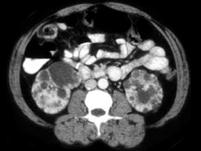

女,35岁,请根据所示图像,选择最可能诊断 ( )A、囊性肾癌B、单纯性肾囊肿C、多发性肾囊肿D、肾癌E、多囊肾

问题 女,35岁,请根据所示图像,选择最可能诊断 ( )

选项 A、囊性肾癌 B、单纯性肾囊肿 C、多发性肾囊肿 D、肾癌 E、多囊肾

答案 E